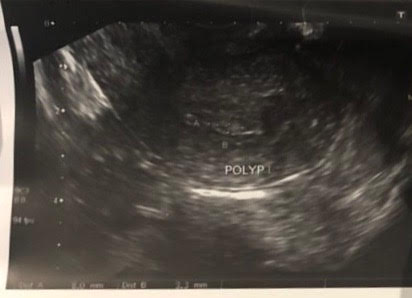

На стимуляции появилось подозрение "полип тела матки / участок гиперплазии эндометрия".

Диагноз : полип церквикального канала.

№15353/18 - среди крови участки эндометрия пролиферативного типа, фрагменты железисто-фиброзного полипа перешейка матки.

Гистероскопия сделана на 17ДЦ. Полип по Узи не видели на 3 и 6 день цикла, заметили только на 10 и 13 день цикла. Врач объяснил, что эндометрий подрастал и стало заметно его уже позже, посколько он был участком без явной ножки.